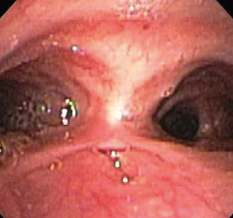

osteomyelitis

Brian T. Kloss, DO, JD, PA-C; Katherine Dougher, MD; Deepak M. Kamat, MD, PhD

<p class="p1"><img src="/sites/default/files/transfer/1208CFP_PCAbscess_A.jpg" width="90" height="90" style="float: left; margin:...